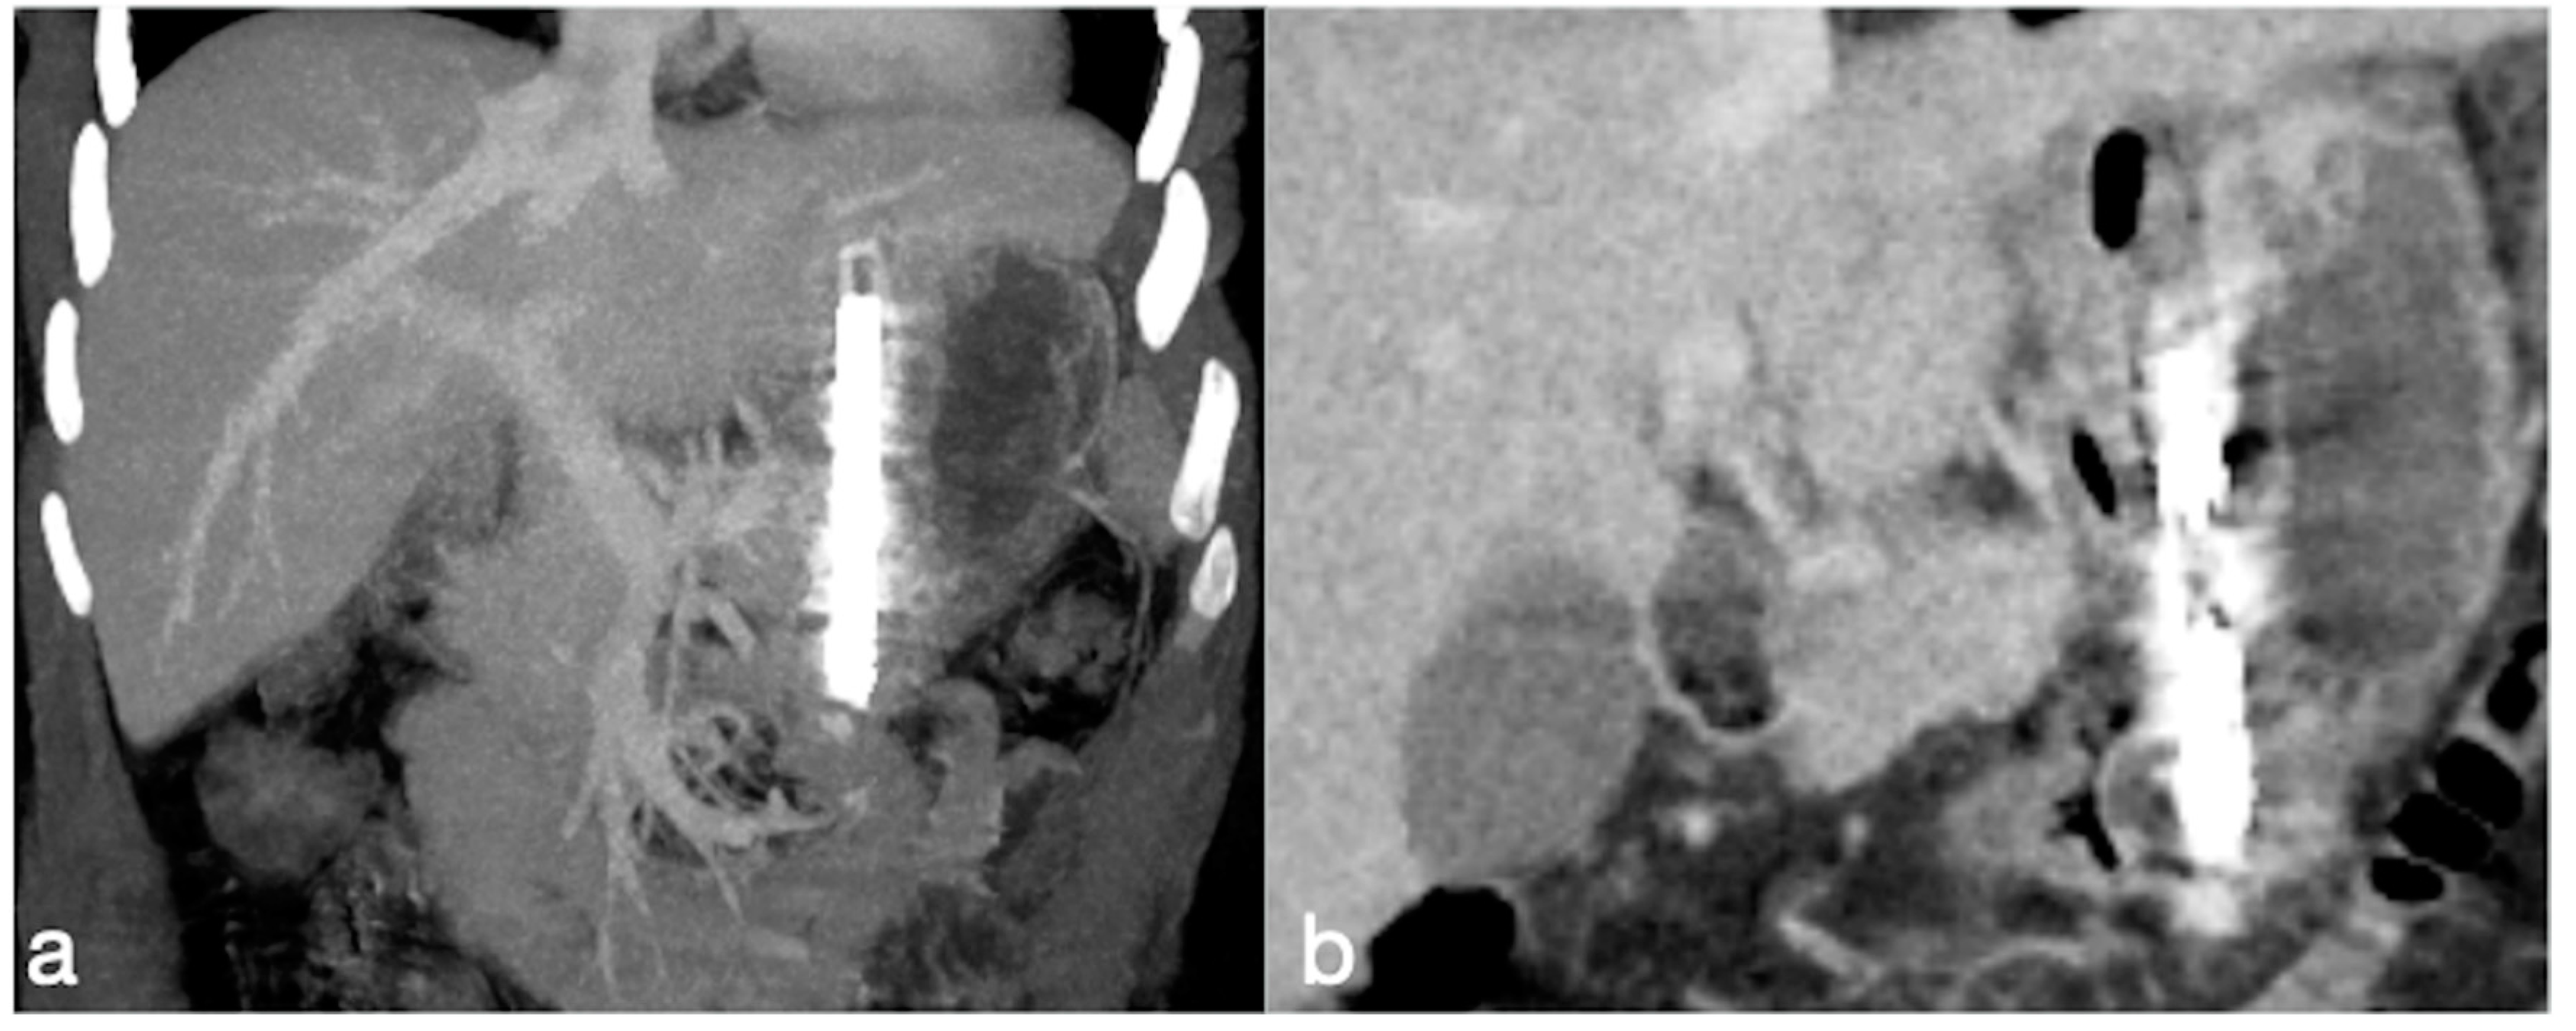

3.3.3. SG

- Leak

- After SG leakage classification

- Gastric dilatation

- Stenosis

- Spleno-porto-mesenteric vein thrombosis (PVT)